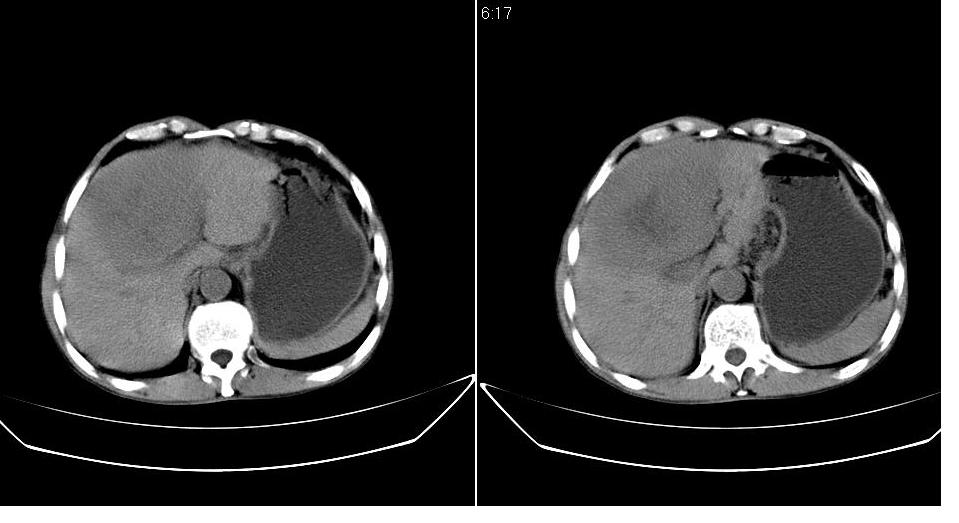

标题: CT20033:上腹部CT平扫

男 66岁,腹疼,b超提示考虑肝癌。

考虑巨块型型肝癌坏死、出血。建议增强。

考虑巨块型肝癌可能性大;建议行进一步检查。

考虑肝左叶巨块型肝癌可能性大;建议行增强ct扫描。

肝癌并门脉癌栓形成。

没完善检查手段,增强后再说,就算你有一万个理由说是肝癌,证据何在?

呼吁从事ct诊断的同志们,腹部占位,特别是肝脏病变没有平扫和三期增强检查,我们底气不足,拿什么来让临床医师信服我们。